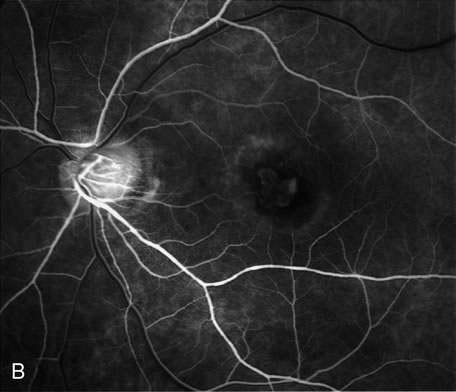

PCV is characterized by the presence of dilated, choroidal vascular channels ending in orange bulging polyp-like dilations in the peripapillary and macular area. Associated features are recurrent subretinal hemorrhage and vitreous hemorrhage, relatively minimal fibrous scarring, absence of retinal vascular disease, pathologic myopia, and signs of intraocular inflammation. FA demonstrates the presence of the dilated vascular channel (Fig. 14 and 15). However, the presence of blood and exudation may block the details of the choroidal circulation on the angiogram. In these cases, ICG angiography can better demonstrate the presence of a distinct network of vessels within the choroid because the larger choroidal vessels are filled with dye.

Fig. 14. A. Color photograph of the right eye shows a ramified pattern of choroidal vascular abnormality irradiating from the peripapillary area toward the macula. The dilated vascular channels end with bulging polyp-like structures. A larger, orange, saccular dilation is seen inferior to the macula (white arrow); leakage of fluid from this vascular abnormality results in serosanguineous pigment epithelium detachment (black arrows). B. The corresponding fluorescein angiogram composite highlights the vascular lesion in the peripapillary area and the serosanguineous detachment of the pigment epithelium that extends inferiorly and temporally off the macula.